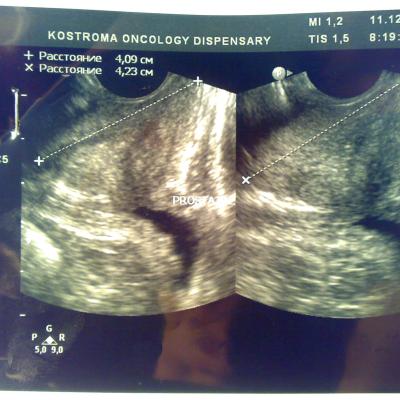

Доброго времени суток. В начале декабря сходил в банное заведение, употребил там пиво, вечером был сексуальный контакт с постоянной партнершей, на утро у обоих появилось жжение при мочеиспускании, у меня покраснение губок полового члена, умеренные выделения прозрачные, анализы крови и мочи в норме, ПЦР у обоих отрицательные. У девушки соэ 28, лейкоциты в моче выше 200, у меня все в норме, бак посев отделяемого из уретры выявил обильный рост Ешерихии коли, принимал внутремышечно Цефотаксим по 1г 2раза в день в течении 5 дней, во время лечения появилось жжение и дискомфорт в промежности. Трузи показало увеличение простаты, расширенные семенные пузырьки около 3 мм, кальцинатов и инфильтратов нет, в область мочевого пузыря не вдается, остаточное количество мочи около 10 мл, кол лейкоцитов в отделяемом из уретры 5-8 в поле зрения. Сейчас принимаю по назначению уролога Нолицин 400 мг по таблетке два раза в день, Палин 250 мг по 1 два раза и азитромицин 250 по одной раз в сутки, свечи на ночь Простатилен курс на 10 дней, уже прошло восемь массажей улучшение незначительное, симптомы в обшей картине сохраняются, железа со слов уролога стала более упругой и меньших размеров. У меня стала страдать эрекция, полной уже нет около 2 месяцев. После эякуляции хочется мочится, неприятные скребущиеся ощущения в промежности, сперма раньше выстреливала, а сейчас вытекает, выстреливает только первая порция, появились боли в мошонке слева, особенно после массажа, подскажите пожалуйста что делать, как лечится, какие еще анализы сдавать. Прикреплены снимки узи.Заранее благодарен.